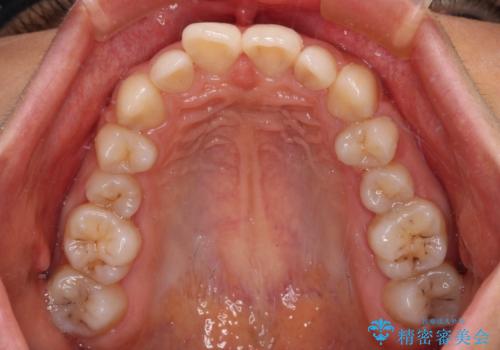

- 後続永久歯の欠損によるスペースと残存乳歯、深い咬み合わせを気にして来院された患者様です。

乳歯を残し、欠損部位のスペースを適正な幅に拡大し、インプラント補綴治療により歯列を整える治療も考えられましたが、ご本人から飛び出している前歯をどうしても引っ込めたいとの要望があったため、残存乳歯ならびに上顎左右第二小臼歯を抜歯して、歯列を整えることとしました。